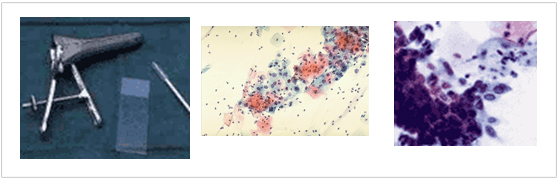

���������˻�(�������˻�)

�ֱٿ� ���� ���ε��� 80-90%���� ������ �˻�� ��Ȯ�� �˻縦 ���� ��õ�ص帮�� �˻� ����Դϴ�.�ڱð���� ������ �˻�� ���Ҿ� �����ϰ� ������� �� �ڱð�� �� ������ ������ ä��, ���̰����� �����Ͽ� �ϼ����� ������ �� �ִ� ����Դϴ�. ��뵵 �ΰ� �˻絵 �����ϸ� �ܽð��� ����� �� �� �ֽ��ϴ�. �ݸ� ä���� �� ���, �˻���� �ǵ��ɷ¿� ���� ����� ��Ȯ���� ������ ���� �ֽ��ϴ�. ��Ȯ���� 80% �����Դϴ�. ���� ��������(�ڱð�ο� �ϰ� ���� �̻��� �������� �������� ������ ���)�� �� 10~30%�Դϴ�.